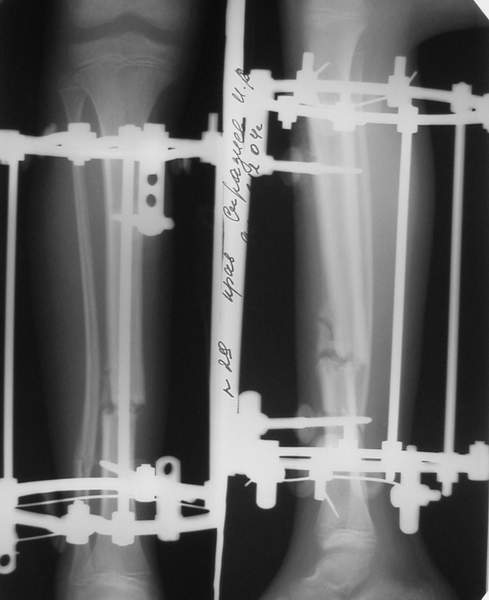

Уважаемые коллеги,Больной 17 лет , 3 недели с момента травмы, был переведен в наше отделение из соседнегогоспиталя.

Попытка закрытой ручной репозиции, предпринятая ранее в этой больнице,оказалась безуспешной, что и явилось причиной перевода к нам.Чтобы вы предложили в данной ситуации?Показана ли фиксация перелома малоберцовой кости в данном случае или в этом нет необходимости?Евгений Чекашкин

В аттачтах №№ 1 и 2 - примеры, когда 2 кольца не позволили послеоперационно

исправить смещение фрагментов большеберцовой (по ширине и вальгусное).

А казалось бы (#2) - поиграй на штангах и все влетит.

Оперировал не я

1

1a